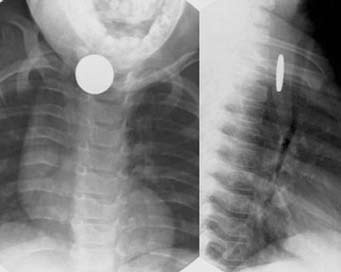

Při podezření na CT v zažívacím traktu je třeba zhotovit rentgenový snímek krku, hrudníku (v projekci předozadní a bočné) a břicha k ozřejmění uložení, velikosti, tvaru a počtu CT (obr. 1). Ale pouze 65 % CT bývá rtg kontrastních. Dřevěná, skleněná, plastová CT, kosti z ryb nebo kuřete nejsou na nativním rtg snímku vidět. Zde je možné zhotovit rtg snímek jícnu a žaludku s vodnou kontrastní látkou k vyloučení defektů v náplni nebo u symptomatických pacientů rovnou provést endoskopické vyšetření horního zažívacího traktu (ezofagogastroduodenoskopii - EGD). Většina požitých CT projde zažívacím traktem spontánně, bez potíží. Pouze u 10-20 % dětí je třeba provést EGD či vzácně chirurgickou intervenci (méně než 1 %). Postup závisí na uložení, velikosti a charakteru CT.